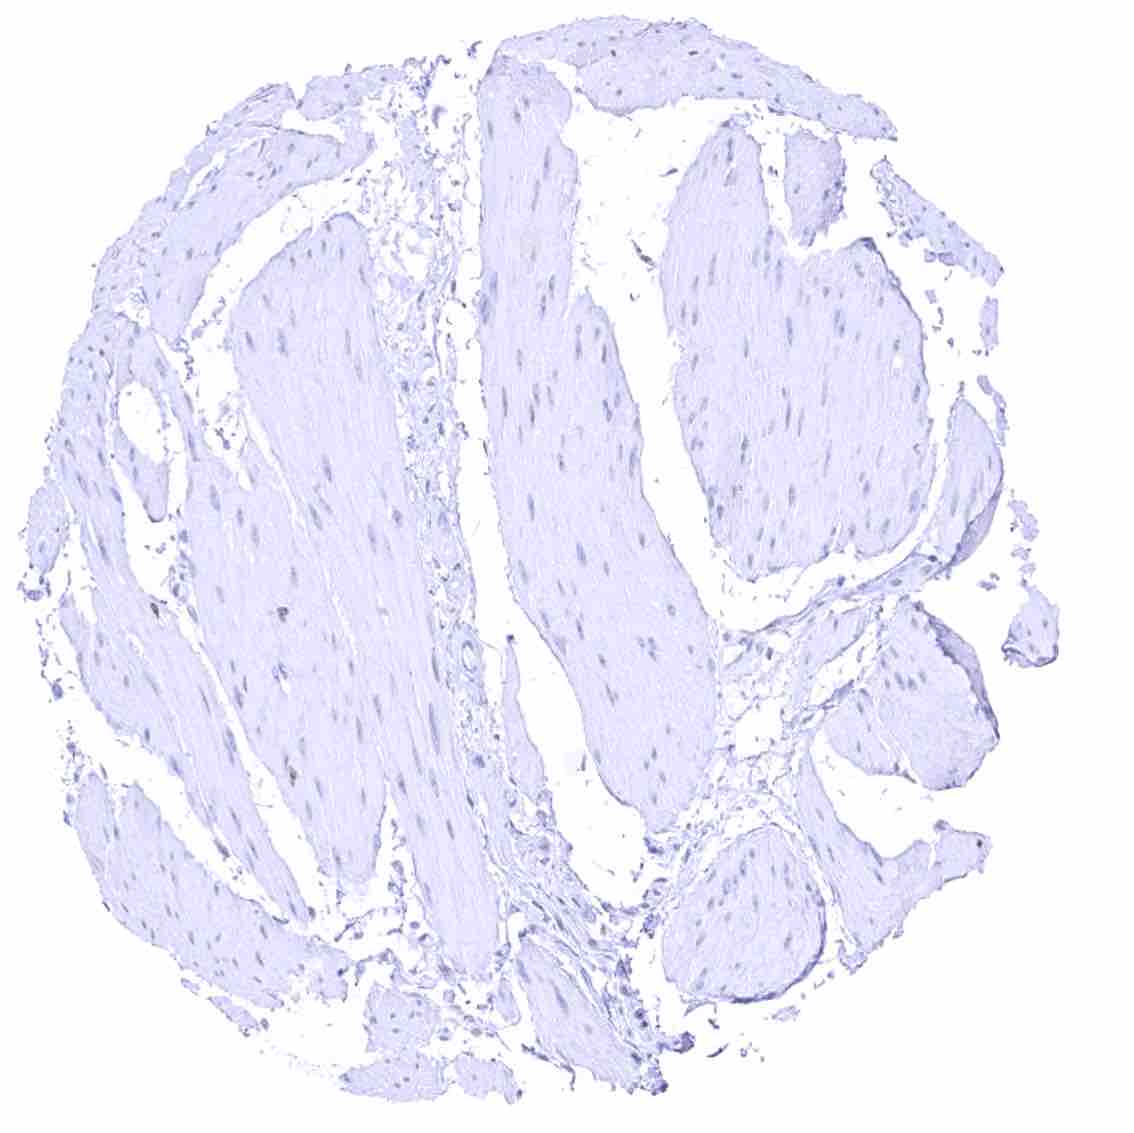

Aorta, media